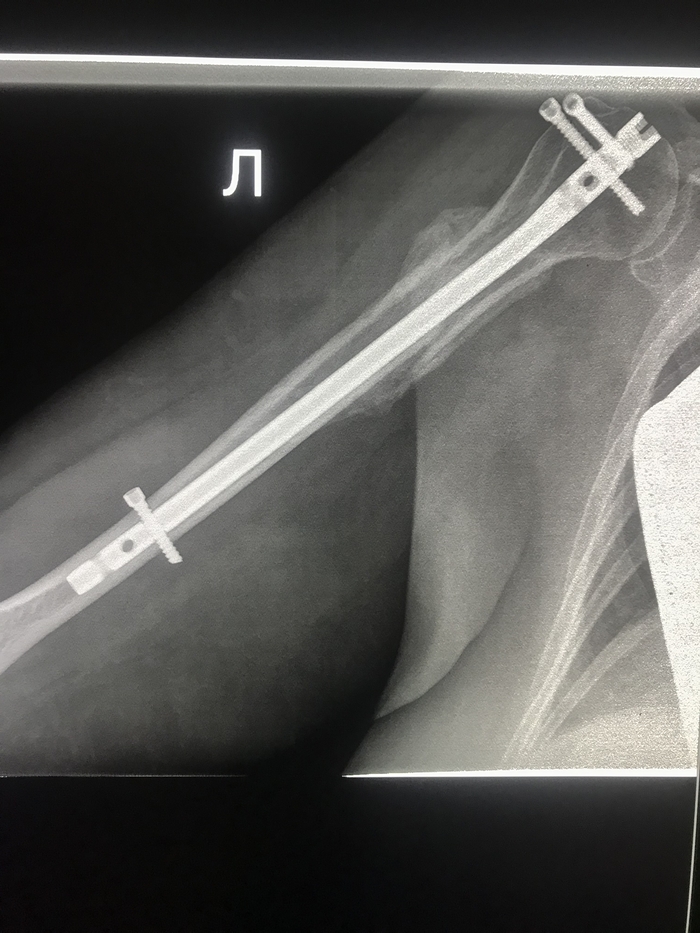

Пластина и штифты на плечевой кости. Перелом произошёл после падения с электросамоката. Восстановление долгое.